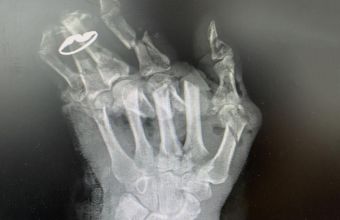

Лікарі констатували: січкарня так сильно понівечила чотири пальці, що врятувати їх неможливо. Сильно постраждала і кисть: множинні переломи, дефекти кісткової та м'яких тканин, а також пошкоджені сухожилля, артерії та м’язи. Аби поборотися за часткове збереження руки, хірурги одразу взялися оперувати пані Галину. Вони зафіксували кістки металевими конструкціями, зшили сухожилля, нерви та артерію, провели пластику м’яких тканин та шкіри. На відновлення всіх структур лікарі витратили близько 4 годин.